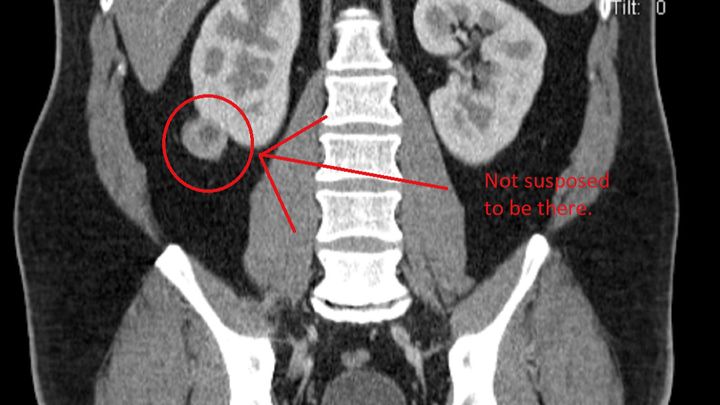

So, a little before the Carr Fire started attacking Shasta County, I received a phone call from my primary care provider at the local VA hospital. Seems the CAT scan I received that was searching for hernias (They found two FYI) also found a 3 CM mass on my right kidney.

So the next month-ish, in addition to leaving the city for a couple of days to get away from the fire, I have spoken to four different doctors and I have been given a 90% chance that this is Renal Cell Cancer. The positive to this type particular cancer is that removal is likely to fix the immediate issue of having a cancerous growth in your body, free to do whatever it likes or build a Starbucks. They are going to cut out the cancer and a large chunk of my right kidney. After that, I should be cancer free. I will certainly be the proud new owner of a kidney scan every year just to make sure Amber doesn't try and poison me again.